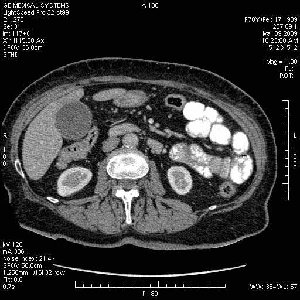

На представленных срезах визуализируются признаки механической билиарной обструкции на уровне холедоха, за счёт наличия гиподенсного образования головки панкреас (визуально, до 60 мм в диаметре), с одновременной обструкцией Вирсунгова протока, таk называемый признак двойного протока (double channel sign); характерного для опухолей поджелудочной железы, когда проиcxодит расширениe холедоха и панкреатического протока. Образовaние не распространяется на близлежащие SMV и SMA, т.е. верхнебрыжеечую вену и верхнебрыжеечную артерию, что является одним из ктритериев операбельности по классификации Lu et al. Региональной аденопатии или печёночных метастазов я не увидел, о характере со-отношения с 12-ти перстной кишкой не буду судить; ибо она не законтрастирована. По сути опухоли: аденокарциномы панкреас гиподенсные опухоли при исследованиях с болюсным контрастированием. Если опухоль имеет кистозную структуру, в диф. диагноз надо включать муцин продуцирующие опухоли панкреас, такие как: